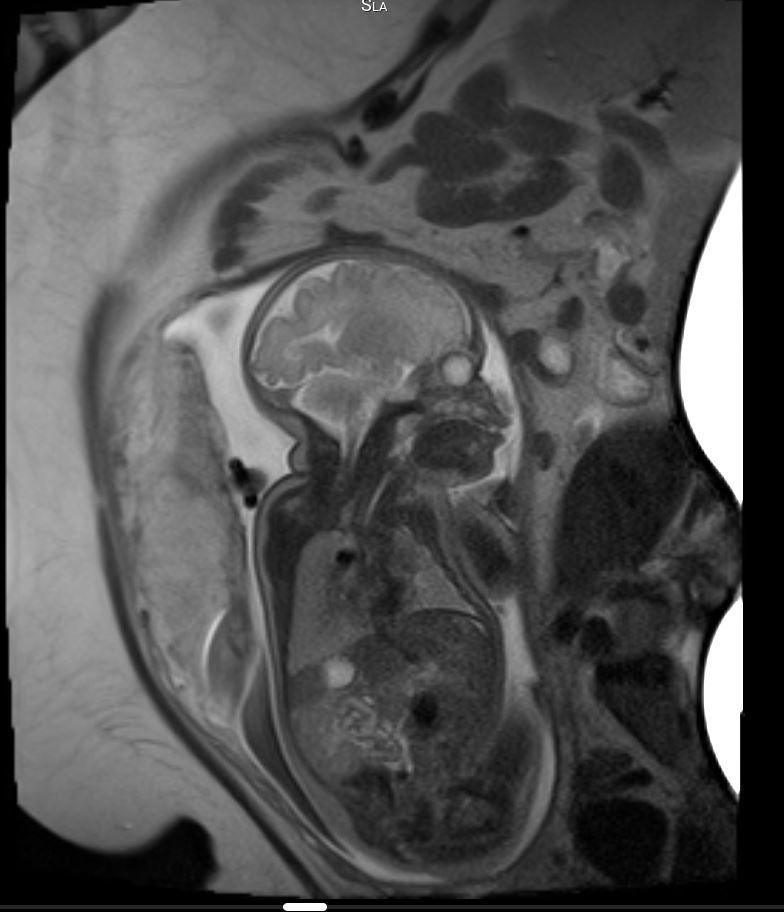

Das fetale MRT (Magnetresonanztomographie) ist ein strahlungsfreies Verfahren, mit dem wir Organe und Strukturen Ihres ungeborenen Kindes besonders detailreich darstellen. Es ergänzt die pränatale Ultraschall-Diagnostik und hilft, Fragestellungen präzise zu klären und die weitere Betreuung zu planen.

- Abklärung von Auffälligkeiten im Ultraschall, z. B. Gehirn, Wirbelsäule, Lunge, Bauchorgane

- Beurteilung von Organreife und Entwicklung, wenn die Sicht im Ultraschall eingeschränkt ist (z. B. mütterlicher Body-Mass-Index, Lage des Kindes)

- Therapieplanung vor/nach intrauterinen Eingriffen oder für die Geburt in einem spezialisierten Zentrum

Unsere Neuroradiologen arbeiten eng mit Pränatalmedizinern, Neonatologen, Pädiatern und Chirurgen zusammen. Modernste Geräte und spezialisierte Protokolle sorgen für hohe Bildqualität – auch bei kindlichen Bewegungen.